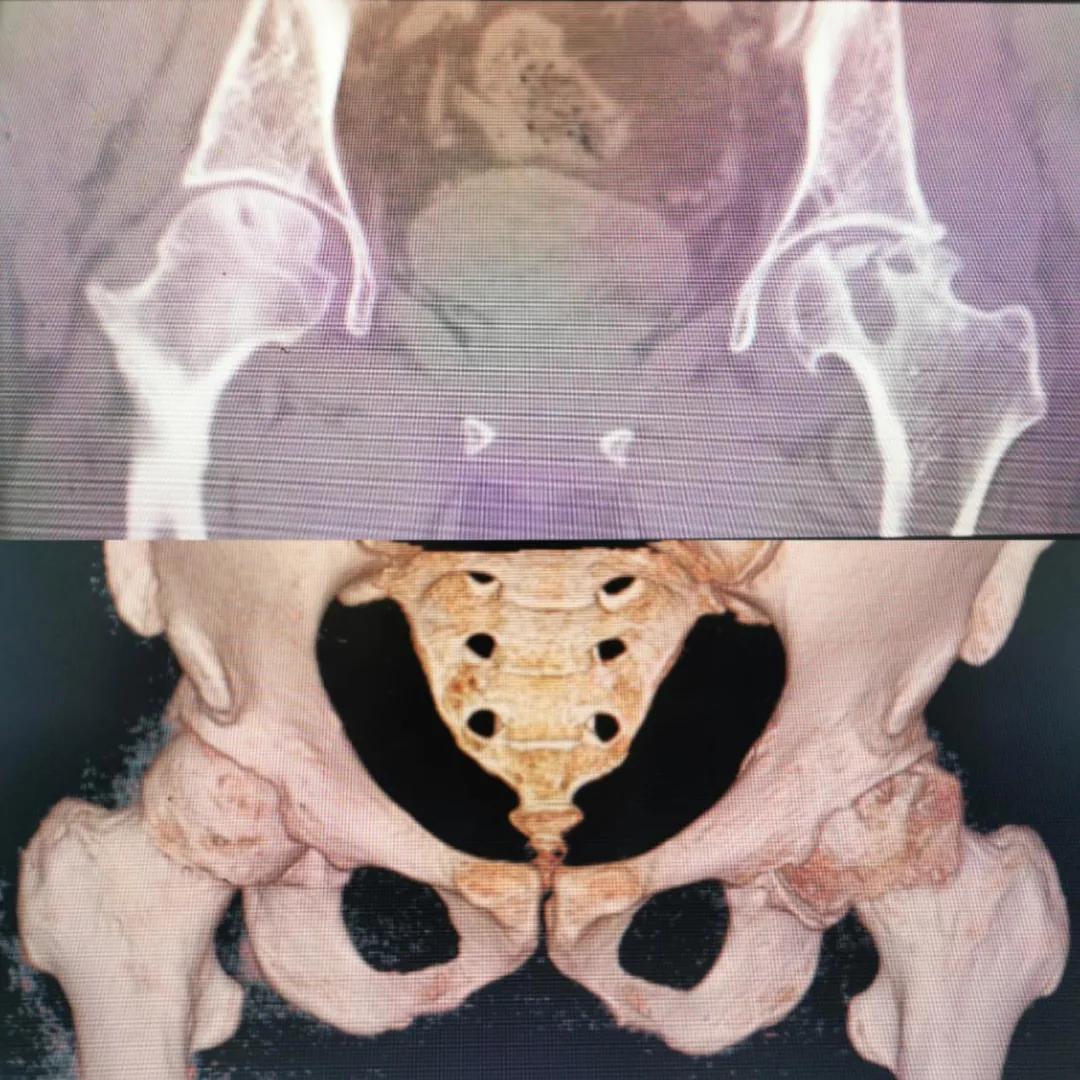

入院急查血結果提示炎癥反應,感染較重,凝血功能及肝功均不同程度損害;髖關節(jié)磁共振(MRI)檢查提示雙側股骨頭缺血壞死,繼發(fā)髖關節(jié)炎,左側髖周軟組織腫脹。醫(yī)療團隊給出的初步診斷為膿毒血癥、股骨頭缺血性壞死、軟組織感染、皮膚潰瘍及閉孔神經(jīng)損傷。

圖片(圖為患者入院時髖部CT檢查)

追溯病史,患者訴前不久曾用蜂蜇療法治療股骨頭壞死,每日4次,每次100只蜜蜂蜇雙臀部、髖部,這才導致了病情急劇進展。查明了來龍去脈,我院智能微創(chuàng)骨科醫(yī)護團隊與患者家屬積極溝通病情,給予特殊級抗生素抗感染以及消腫、止痛等支持治療,同時對潰瘍創(chuàng)面進行專業(yè)、規(guī)范的清創(chuàng)、換藥處理,保護創(chuàng)面降低感染程度;護理上輔助翻身,減少壓力性損傷。